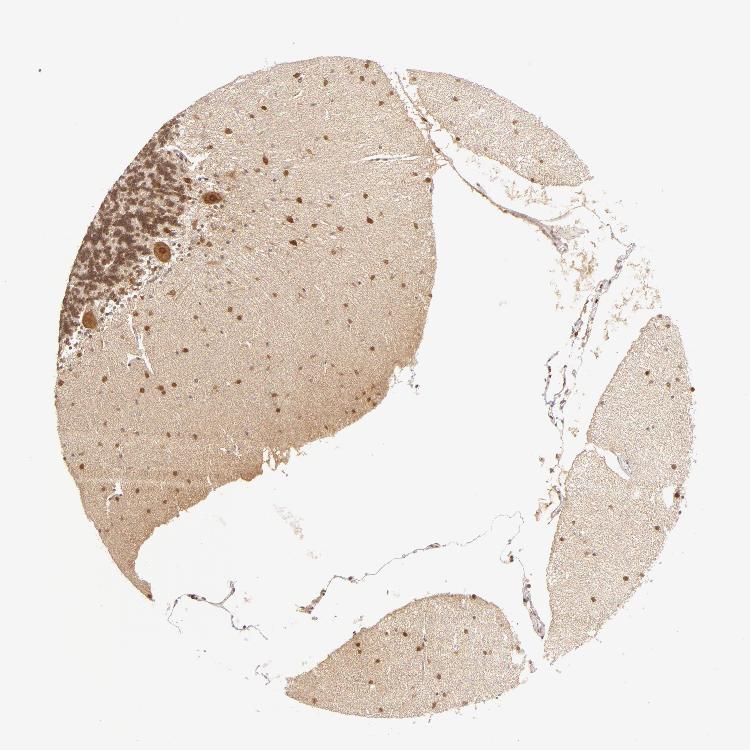

BRAIN CEREBELLUM Show tissue menu

CEREBELLUM - Expression summary

CEREBELLUM - Antibody stainingi

Antibody staining in the annotated cell types in the current human tissue is reported as not detected, low, medium, or high, based on conventional immunohistochemistry profiling in selected tissues. This score is based on the combination of the staining intensity and fraction of stained cells.

Each image is clickable and will lead to virtual microscopy that enables deeper exploration of all samples and also displays staining intensity scores, fraction scores and subcellular localization as well as patient and tissue information for each sample.

Antibody CAB002213

Purkinje cells High

Cells in granular layer High

Cells in molecular layer High